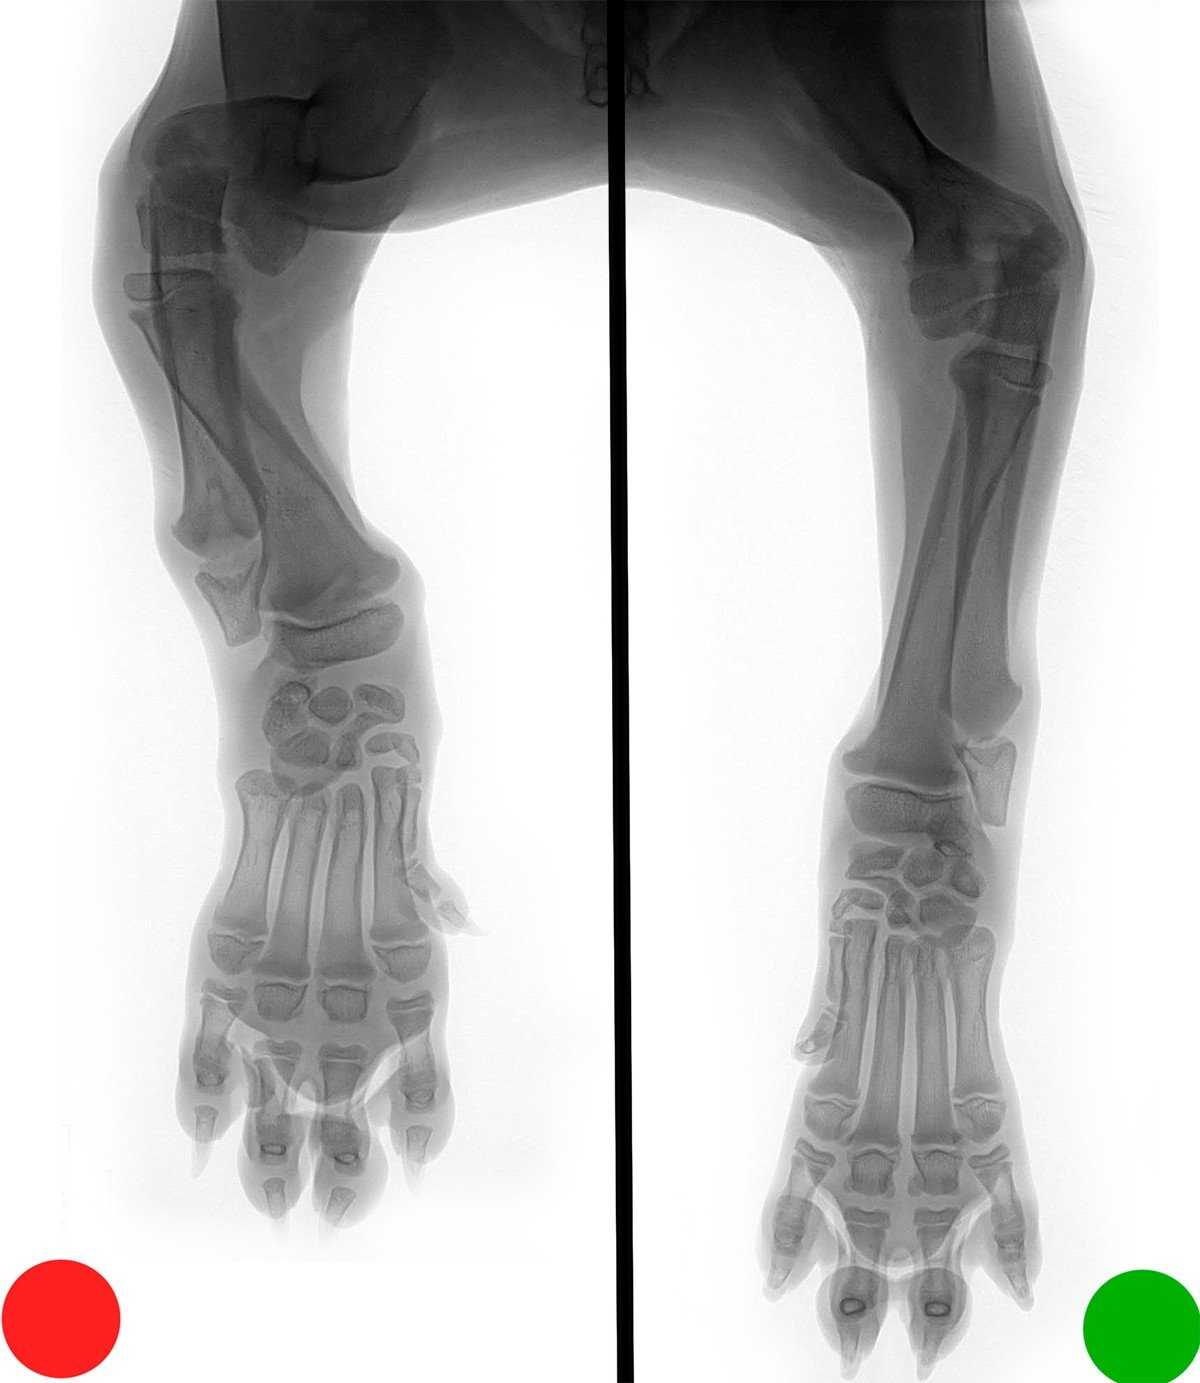

Рентгенографический снимок двух щенков одного возраста. У одного из них хондродисплазия передних конечностей, помечено красным.

НО! Если преждевременно заканчивает рост только одна из костей предплечья, в этом случае щенка ждут боли и страдания. Поскольку вторая продолжает расти, она со временем искривляется, часто ломается. Страдают суставы, мышцы, вся лапа собаки. В этом случае можно помочь только хирургическим вмешательством.